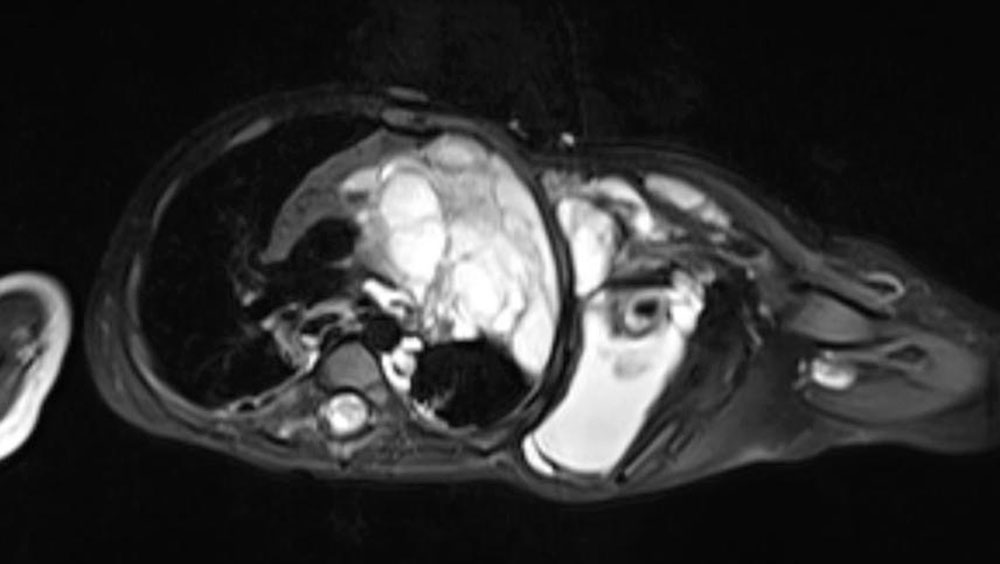

Retroperitoneale LM können jahrelang unbemerkt bleiben. Oft, wieder im Rahmen eines Virusinfektes, schwellen kleinere zu größeren Zysten an und verursachen Symptome (Schwellung des Abdomens, intraabdominelle Schmerzen). Es sind schon derartige LM bei Operationen unter dem Verdacht einer Appendicitis oder Hydrocele entdeckt worden. Intraabdominelle LM befallen meist das Mesenterium des Darms und verursachen tastbare Resistenzen im Bauchraum oder Darmpassagestörungen.